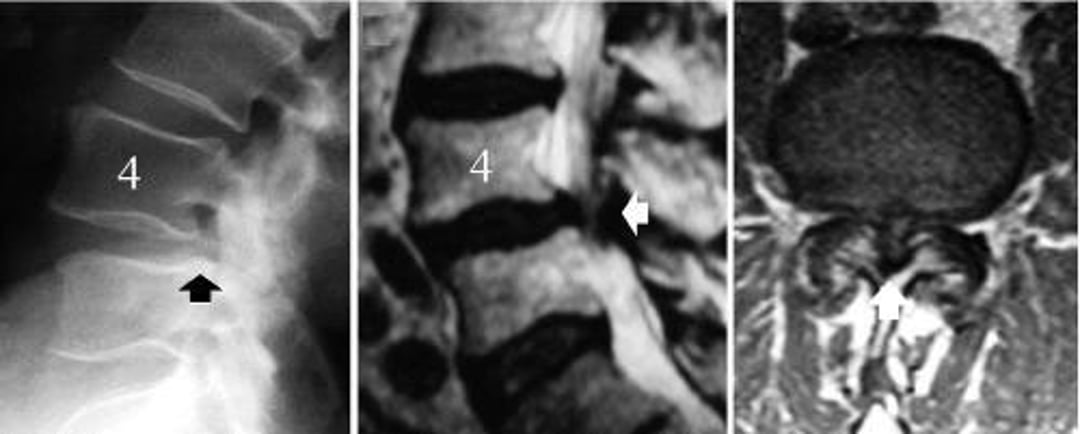

Стеноз поперекового відділу хребта, спричинений дегенеративним спондилолістезом L4-L5

The image on the left is a lateral radiograph of the lumbar spine showing slipping of the L4 vertebra (black arrow—the posterior border of the L5 vertebral body does not align with that of L4). The image in the middle is a midsagittal MRI scan showing compression of the neural structures (white arrow). The image on the right is an axial MRI scan showing severe spinal stenosis at the level of the degenerative spondylolisthesis, L4-5 (white arrow).